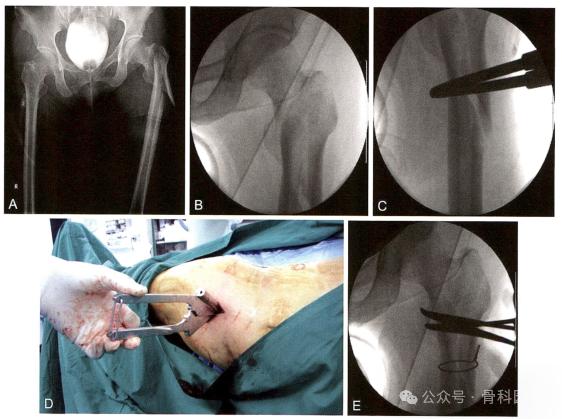

复位技术二(参考实用髓内针治疗学:王秋银主编2023年)

1、

2、

3、

4

5、